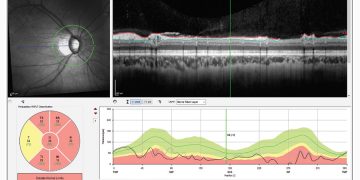

Glaucoma